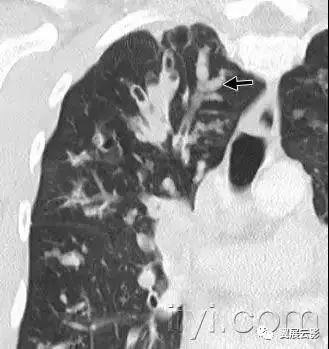

七十一、牵拉性支气管扩张或者细支气管扩张

CT:牵拉性支气管扩张和细支气管扩张是由于周围肺纤维化牵拉导致的支气管和细支气管的不规则扩张。扩张的气道可以如图所示,可以是囊状(支气管)或者是小囊状(细支气管)。多发囊样气道变形与单纯性纤维化所致蜂窝征难以鉴别。